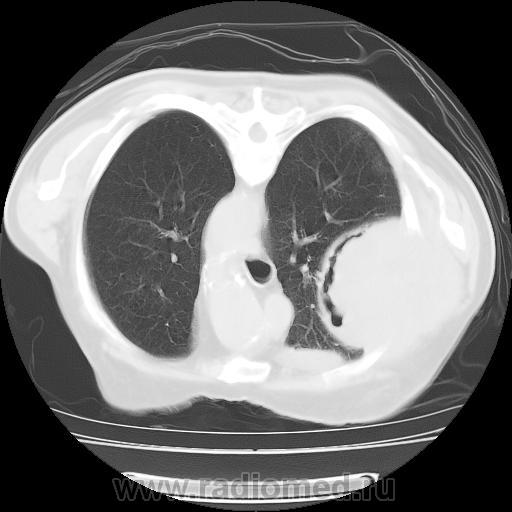

Правое легкое: в проекции средней доли (S3,4,5) определяется объемное образование преимущественно однородной структуры с ровными, четкми контурами размерами 92х88х94мм. Плотность его составляет 19-25 едН. В медиальных отделах образования содержится серповидная полоска воздуха. Латеральные отделы образования выходят за контуры грудной полости на 42 мм. На этом участке ребра не дифференцируются. Внутренний контур передней зубчатой, подлопаточной мышц размытый, граница между образованием и ними отчетливо не видна. Кзади от образования, в кортикальных отделах в легочной ткани инфильтрация. Кпереди от описанного образования расположен участок, широким основанием прилежащий к грудной стенке, имеющий плотность 12-20 ед.Н, однородную структуру, размеры 14х48мм. Прилежащее ребро интактно.

И возникла совершенно шальная мысль. А где располагается "ЭТО"? В легочной ткани или нет? и умозрительное продолжение контуров "ЭТОГО", показало, что "ЭТО" выходит за пределы грудной клетки, а именно костных её компонентов, что находит подтверждение на отдельных сканнах.

А не экстраплевральная - ли "ЭТО" пломба, которая была применена по типу "олеоторакса"?